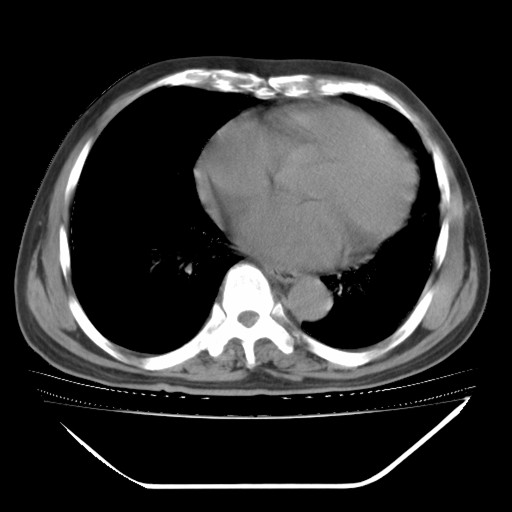

以下是引用hhcckk在2009-5-29 10:34:00的发言:[br]左下肺片絮状边缘模糊影,考虑感染,建议治疗后复查[br]